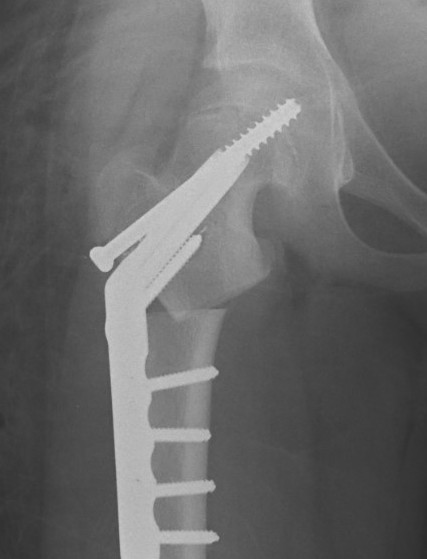

Intertrochanteric / Southwick

Technique

Removal anterolateral bone wedge below lesser trochanter

Valgising / flexion / internal rotation